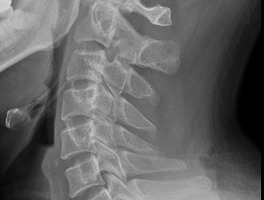

그밖의 이야기/유용한이야기 [좋은글]스스로 나를 발전시키는 13가지 Yasu 2016. 11. 7. 좋은 글이 있어서 퍼옴~ 자주 되새김하며 실행하자! 출처: http://cast.yanolja.com/detail/7934 공유하기 게시글 관리 사진 그리고 일상... 저작자표시 비영리 변경금지 (새창열림) '그밖의 이야기/유용한이야기' 관련글 알콜성 치매.. 올해에는 술,담배를 줄여야겠다.. 자기집안 호칭정리,가족호칭,촌수호칭,직계 내종간 외종간 계촌법,친인척간 계촌법 총정리 가족호칭,촌수호칭,직계 내종간 외종간 계촌법,친인척간 계촌법 총정리 거북목 증후군..(일자목, 목디스크)